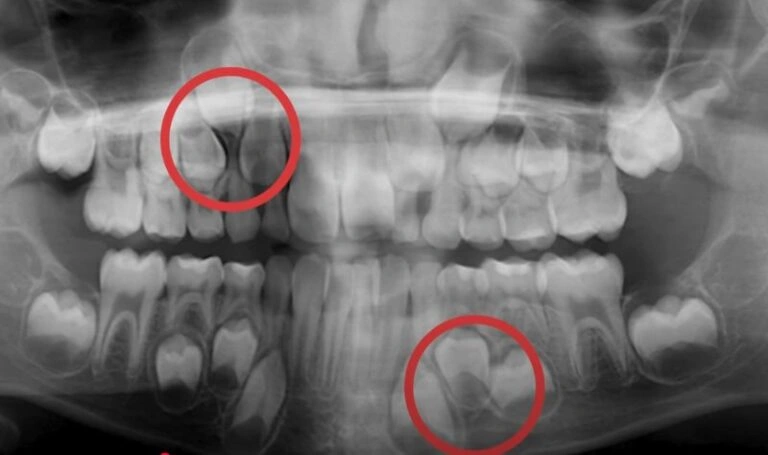

In some cases, the roots of the baby teeth don’t dissolve as they should, keeping them firmly in place. If the permanent tooth beneath isn’t growing in straight, it won’t apply enough pressure to push the baby tooth out. We often see this in kids with crooked or crowded teeth. A quick X-ray can tell us if this is the issue. See the case of Barret, a pediatric patient of mire below!